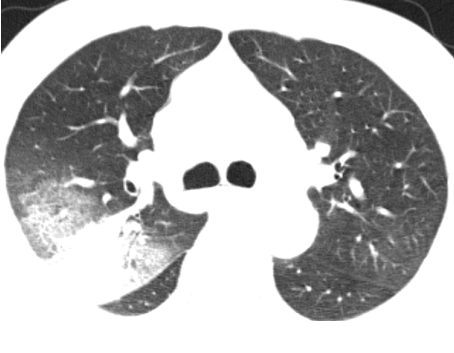

入住肺病科(呼吸内科)后,医生为患者完善了胸部CT及相关检查。影像结果显示:“双肺见片状密度增高影及实变影,边界模糊,提示双肺感染。”针对患者病情,科室立即组织了病例讨论。专家们凭借着深厚的医学知识和丰富的临床经验,深入分析病情,制定出了科学合理的诊疗方案,一天内完成了相关检查。

治疗前CT影像▲